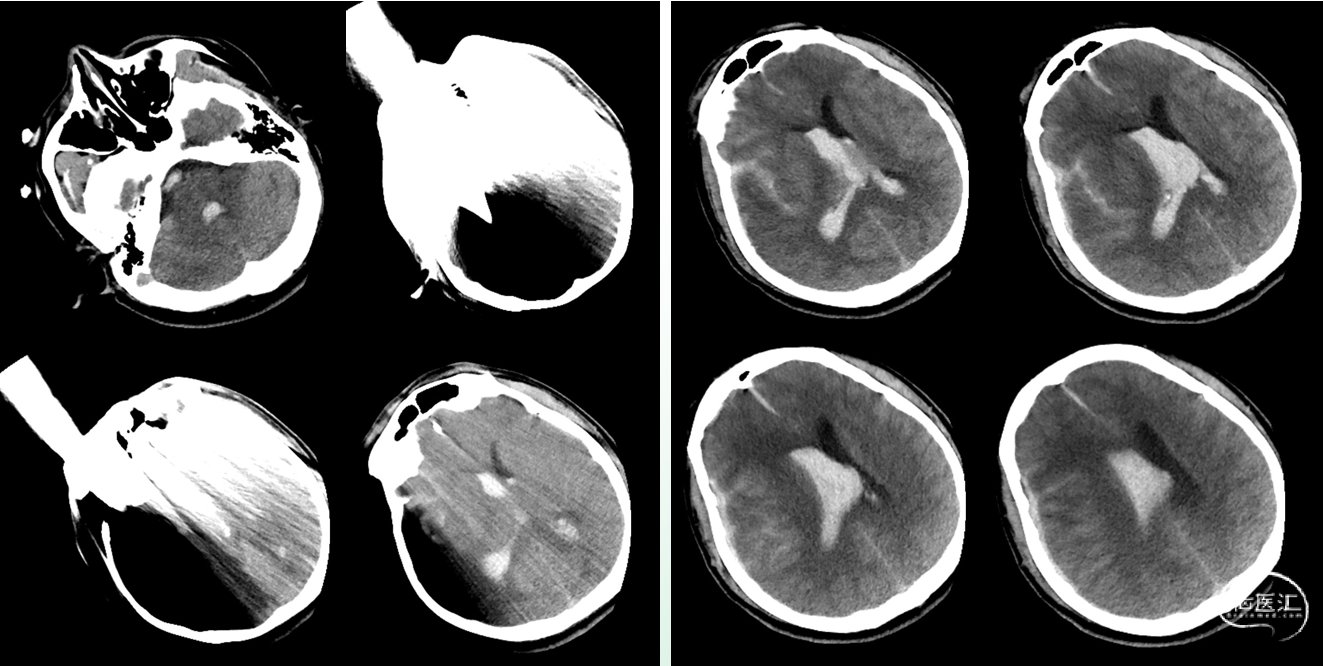

入院时影像

急诊颅脑CT+三维重建:

颅脑锐器损伤并异物存留,异物由右侧眼眶刺入颅内;右侧额颞叶挫裂伤并血肿形成;蛛网膜下腔出血;脑室系统较多积血;右侧额颞顶部少量硬膜下积血